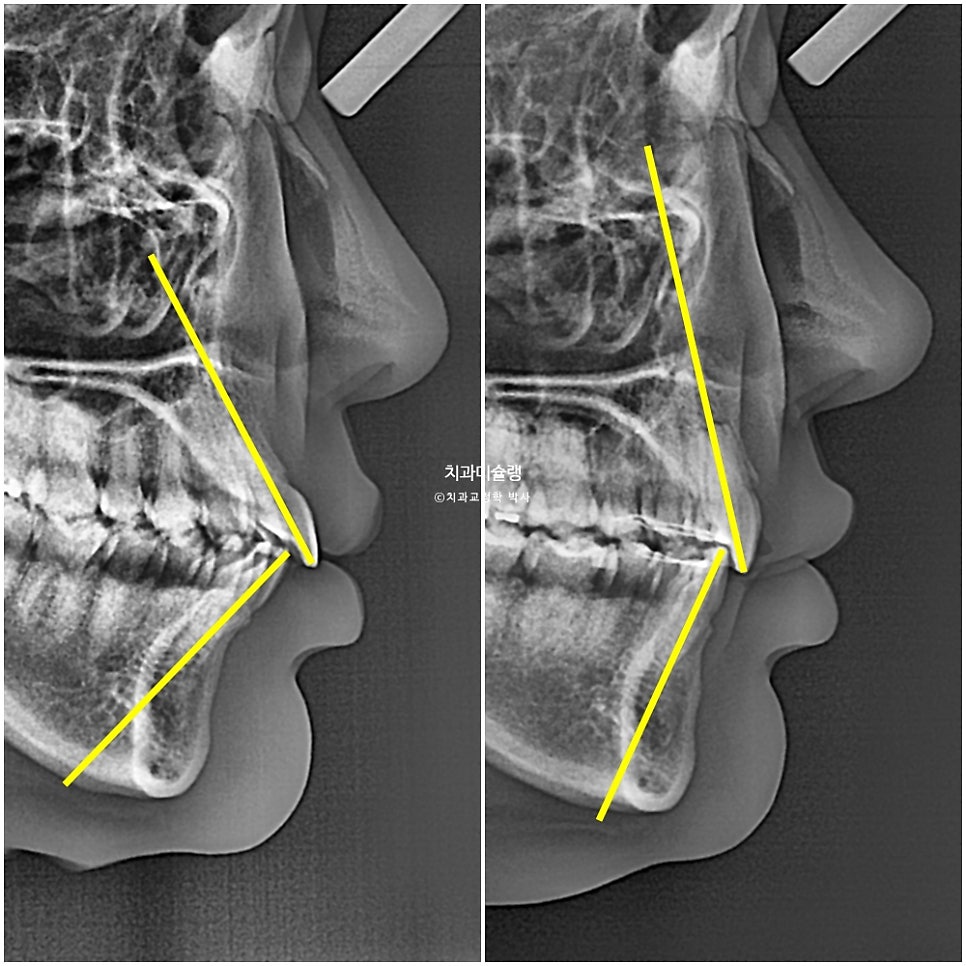

엑스레이로 보면 치근흡수는 없었으며 치아 뿌리 평행도는 좋습니다.

옆모습 엑스레이에서 앞니 각도의 개선이 확인됩니다.

발치교정 후 너무 들어가거나 치아 각도 손실 없이 입매 부작용 없는 치료계획으로, 실패없는 발치교정을 추구합니다.